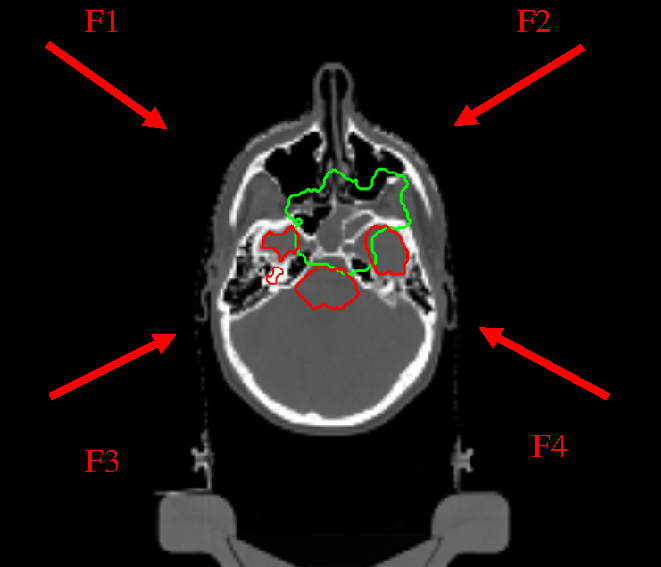

The strategy followed in the nominal treatment (PLAN-NOM) was to draw safety volumes around the metallic rods and to apply hard dose constraint to such volumes of interest (VOIs), as shown in Fig.2, such that the pencil beams of the four fields (F1, F2, F3, F4) involved in the treatment were safe from hitting the rods.

The plan has been re-calculated by replacing the safety VOIs and related dose constraints with the effective contours of the rods, set with OL = 1. In a first attempt, the direction of the fields were kept the same (PLAN-OL-1) and , then, an other plan was generated by considering a wider angular spacing between F1-F2 and F3-F4 (PLAN-OL-2). The angular increase of the new fields with respect to the nominal ones was of 10°.

Refer to caption

Figure 2: Patient with metallic cage: nominal IMPT dose distribution; inside the patient volume, the green contour corresponds to the PTV and the red ones to the OARs; otuside the patient volume, the safety VOIs and the effective countours of the 4 metallic rods are visible; the fields F1, F2, F3, F4 used for PLAN-NOM and PLAN-OL-1 are also shown.